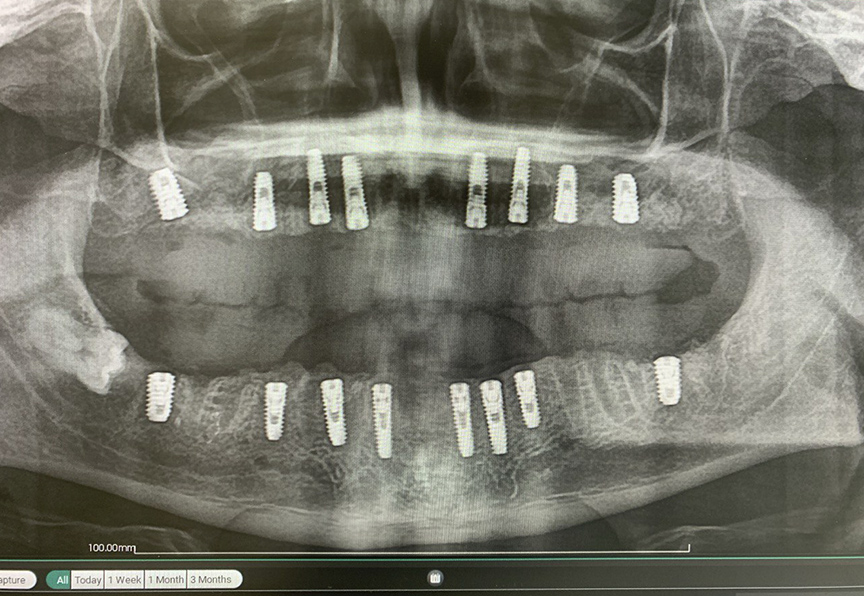

Подготовку к имплантации мы начали через 2 недели после консультации. Я выбрал протокол All-on-8, «Все-на-8». В ходе операции я удалил 25 зубов, одномоментно установил 16 имплантатов Osstem (8 в верхней челюсти и 8 в нижней) и провел редуцирование костной ткани – ее выравнивание по высоте. Для этого я использовал как костный материал (собственную кость пациента из угла нижней челюсти), так и 10-15 коллагеновых губок.

Через год я провел осмотр пациента К. т сделал контрольная ортопантомограмма. На снимке видно, что костная ткань сохранена в полном объеме. Пациент очень доволен итогом лечения, у него нет никакого дискомфорта, улыбка выглядит красиво и естественно. У К. хорошая гигиена, он следит за состоянием полости рта, поэтому моя рекомендация – раз в год посещать профилактический осмотр, делать ортопантомограмму и проводить профессиональную гигиену (тоже раз в год).

Панорамный снимок пациента К. во время визита в клинику через 1 год после лечения. Как видим, все отлично: